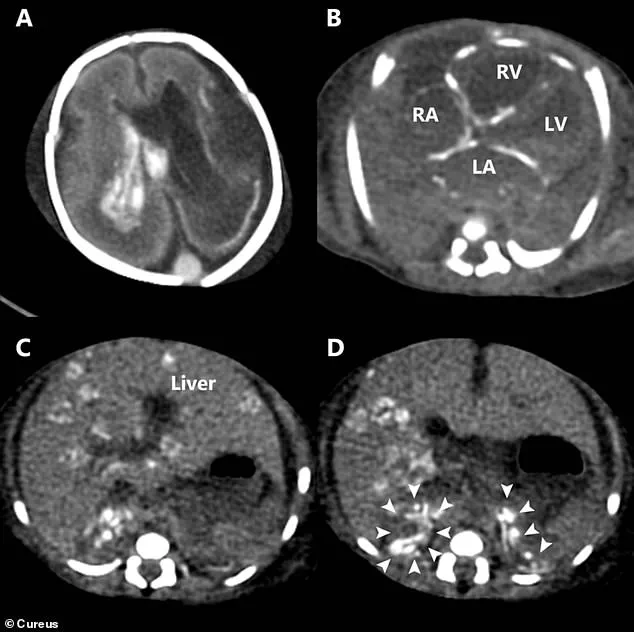

These images from a scan after the baby's death show how the herpes infection caused catastrophic damage throughout his entire body.

A) Bleeding inside the brain's fluid-filled chambers (ventricles).

One chamber is also enlarged.

B) Abnormal, dense spots (calcifications) are visible in the walls of the heart's chambers.

C) Widespread, round, dense spots throughout the liver, indicating tissue damage. (D) Heavy, dense areas in both of the small adrenal glands (located on top of the kidneys), showing they were also severely affected.

A post-mortem CT scan provided the final confirmation of the infection's destructive path.

The post-mortem CT scan revealed multiple areas of overload of calcium in his tissue, a sign of severe, chronic inflammation, throughout the walls of his heart, liver and adrenal glands.

There was bleeding into the fluid-filled spaces, ventricles, within his brain.

Specifically, the case report noted the bleeding due to its inability to clot was in the left lateral and third ventricles, confirming a disseminated HSV infection that began in the womb.